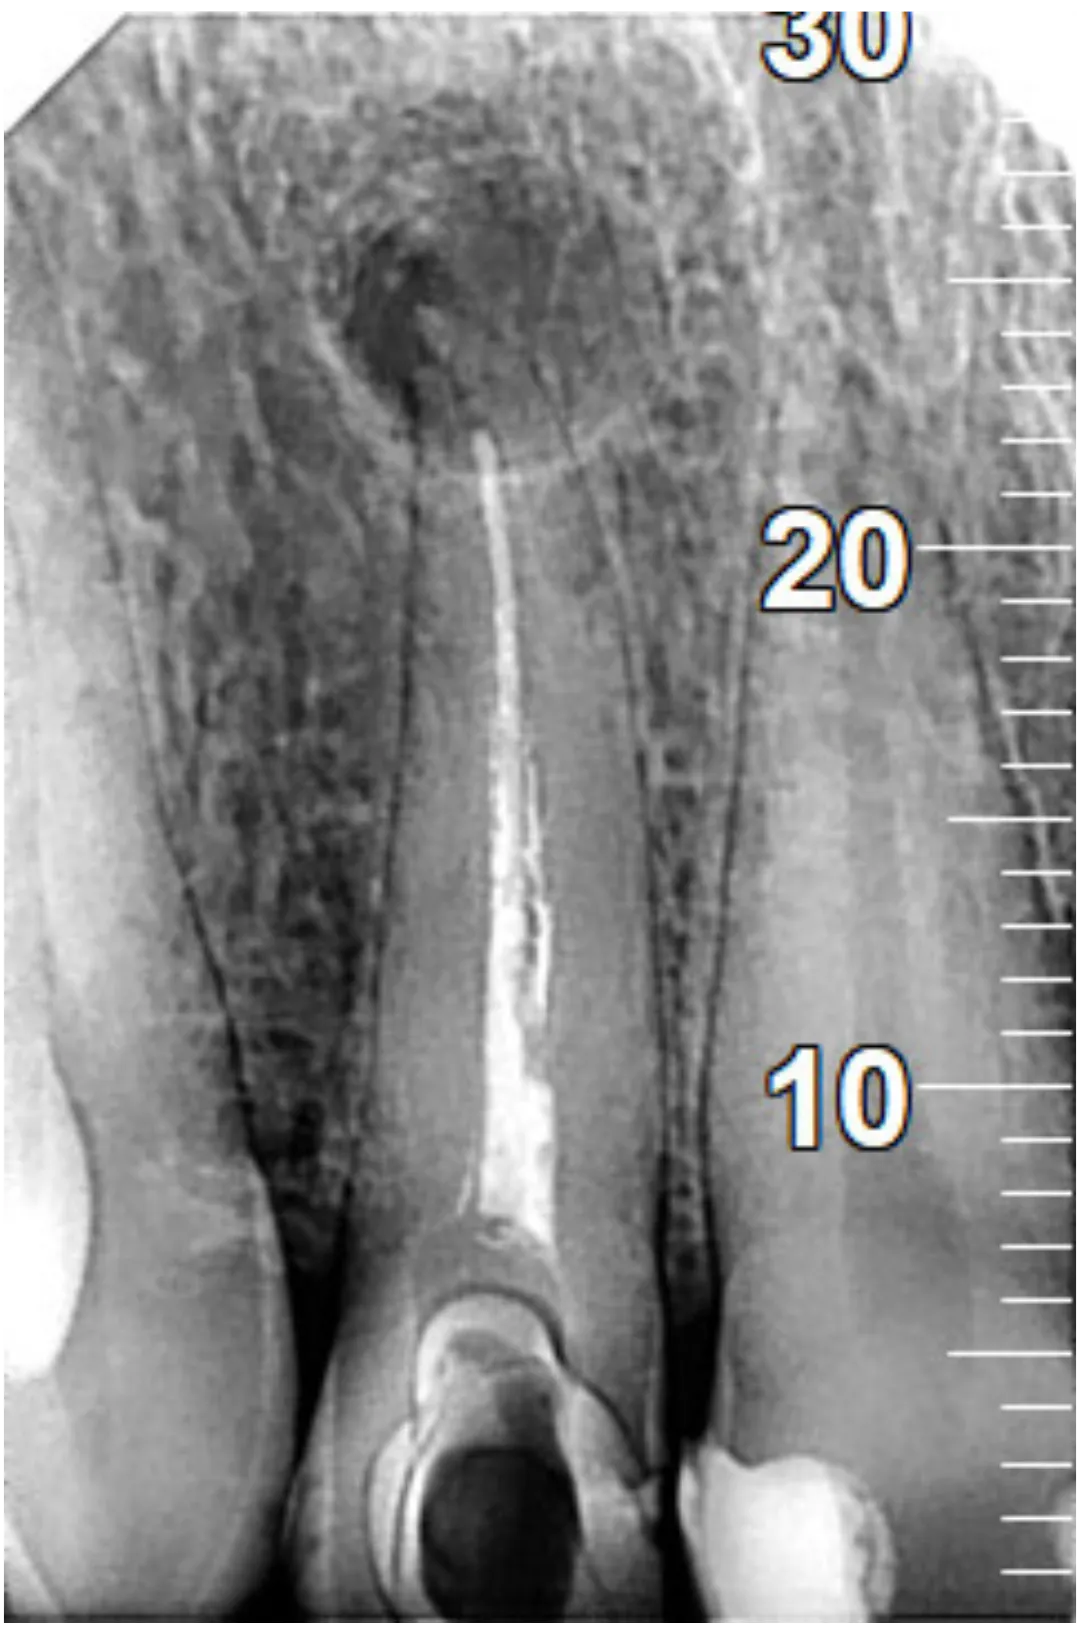

RXDC efikasnost proizlazi iz kombinacije napredne tehnologije i izvanredne sposobnosti za proizvodnju slika visoke definicije. RXDC X- ray uređaj pruža vrhunske performanse, praktičnost i tehnologiju. RXDC se odlikuje generatorom konstantnog potencijala visoke frekvencije (DC) i vrlo malom fokalnom tačkom (0,4 mm) koja omogućava oštre i detaljne slike, istovremeno osiguravajući radnu udobnost i niske doze zračenja za pacijenta.

Veće performanse sa RXDC, rendgenskim uređajem koji kombinuje slike visoke definicije, ergonomski dizajn i niske doze zračenja.

SUPERIORNA DIJAGNOSTIČKA KVALITETA Dobijena u samo nekoliko jednostavnih koraka, sve slike su visoke rezolucije.

NAPREDNA TEHNOLOGIJA

NewTom RXDC rendgenski uređaj visoke frekvencije baziran je na NewTom-ovom znanju, sa udaljenošću izvora od 30 cm i fokalnom tačkom od 0,4 mm.

MINIMALNA DOZA ZRAČENJA

Zahvaljujući pravougaonom kolimaciji i ECO Mode parametrima,

izloženost pacijenta X-zracima je minimalna.